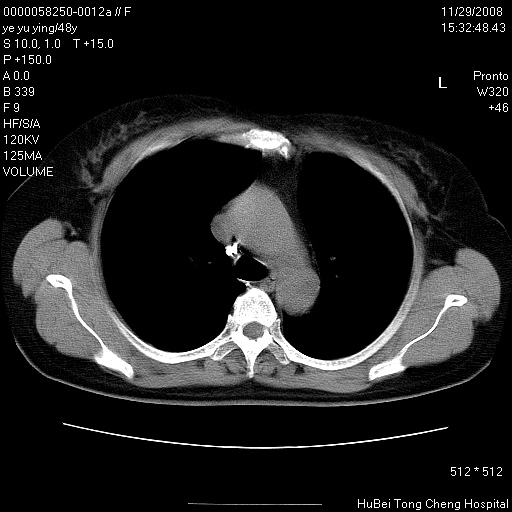

以下是引用zsl6918在2008-11-29 21:47:00的发言:[br]恶性肿瘤病史,转移瘤首先考虑。脂肪肝,胆囊结石。

以下是引用huenhao在2008-11-29 22:11:00的发言:[br]脂肪肝,胆囊结石。左肺病灶建议定期复查。

以下是引用liuyue在2008-11-30 5:44:00的发言:[br]1.左肺病变,首先考虑感染性病变,转移待排;建议治疗后复查。[br]2.肝脏密度普遍减低,考虑与化疗有关。[br]3.胆囊结石.